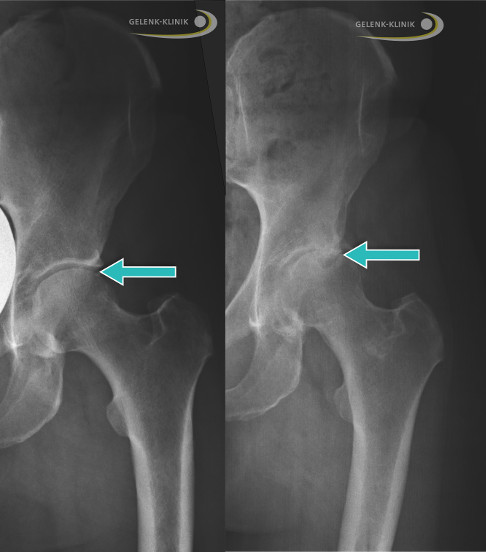

- Hüfte (Coxarthrose)

- Klinik + Röntgen: Gelenkspaltverschmälerung, Osteophyten, Sklerose, Zysten

- Typisch: Knie (Gonarthrose), Hüfte (Coxarthrose), Hände (DIP/PIP), WS

- Röntgen: Gelenkspalt ↓, Osteophyten, Sklerose, Zysten